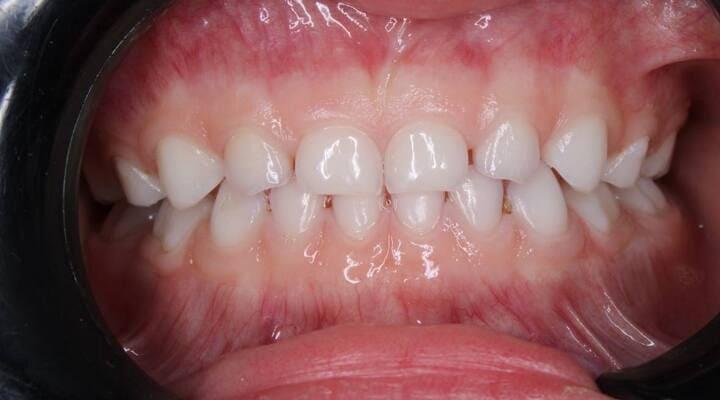

Пацієнт 2 років, уражено десять зубів, шість із яких потребують покриття коронками. В зв’язку зі значним об’ємом та складністю лікування прийнято рішення про лікування в умовах анестезіологічного забезпечення. Раніше була спроба пролікувати ці зуби застарілими методами, які не тільки не є ефективними відносно лікування, а ще і додають дитині комплексів через характерне фарбування зубів. Через високи естетичні вимоги дитини і батьків було прийнято рішення покривати естетичними цирконієвими коронками, як передні так і бічні зуби. Через 2,5 години дитина без інфекції в порожнині рота, з відновленим здоров’ям та естетикою посмішки може кусати, жувати, посміхатись без болю та дискомфорту. Останнє фото через 2 роки після лікування, оскільки естетичні коронки в дитячій стоматології - це надійність, естетика та функція.